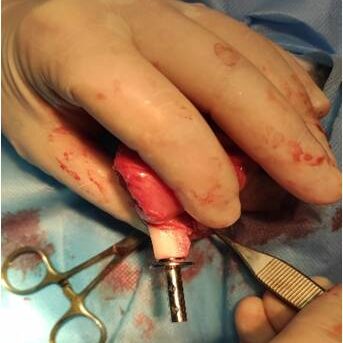

Για την εφαρμογή του εμφυτεύματος τύπου ITAP απαιτείται χειρουργική επέμβαση, καθώς η εφαρμογή του είναι ενδοοστικά. Ένα μέρος τοποθετείται εσωτερικά του ακρωτηριασμένου οστού, στον μυελό των οστών, ενώ το υπόλοιπο εξωτερικό μέρος έχει υποδοχές για να φιλοξενήσει το έξω-προσθετικό, δηλαδή το τεχνητό μέλος (πατουσάκι).  Η Bio3Dvet μέσω του εξοπλισμού αλλά και της εμπειρίας της στον τομέα αναλαμβάνει τον σχεδιασμό, την κατασκευή αλλά και την χειρουργική εφαρμογή των εμφυτευμάτων, σε οποιοδήποτε περιστατικό κριθεί υποψήφιο για χρήση εμφυτεύματος ITAP.

Στη συνέχεια, γίνεται πιλοτική προσομοίωση προ-εγχειρητικά της εφαρμογής του οστού/εμφυτεύματος/έξω-προσθετικού με τα ακριβή ανατομικά πρωτότυπα μοντέλα, εξερευνώντας τα διαφορετικά στάδια υλοποίησης της και μελετώντας όλα τα πιθανά σενάρια.  Η κατασκευή του εξατομικευμένου εμφυτεύματος τύπου ITAP γίνεται με χρήση υπερσύγχρονου μηχανήματος κοπής CNC.

Η διαδικασία ολοκληρώνεται με την χειρουργική επέμβαση όπου το εμφύτευμα, τοποθετείται στο ακρωτηριασμένο οστό. Το χειρουργημένο άκρο θα πρέπει να προστατευθεί για 5-6 εβδομάδες πριν από την εφαρμογή του έξω-προσθετικού. Σύμφωνα με αποτελέσματα περιστατικών άλλων χωρών, η βιολογική ενσωμάτωση των οστικών και δερματικών ιστών με εμφύτευμα τύπου ITAP κρίθηκε αξιόπιστη και ανθεκτική.